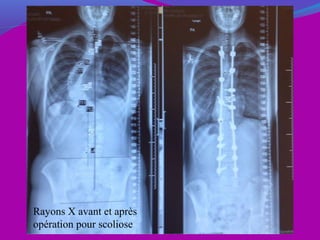

Rayons X avant et après

opération pour scoliose